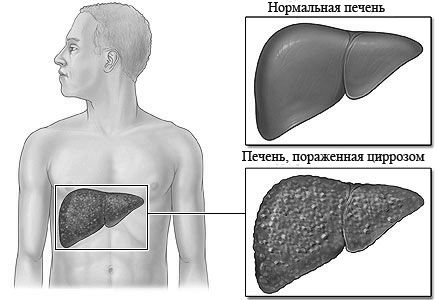

Це захворювання є результатом перенесеного вірусного, алкогольного гепатиту, жирового гепатозу, інших хронічних та спадкових патологій. Це важке захворювання, яке характеризується втратою печінкою її основних функцій, що пов'язано із заміщенням її тканини сполучною. При цирозі спостерігаються такі ознаки:

- печінкові долоні,

- болить печінка,

- печінковий запах з рота,

- порушення згортання крові,

- енцефалопатія (порушення орієнтації, пам'яті, критики до себе і оточуючих),

- гінекомастія (збільшення грудних залоз у чоловіків),

- порушення свідомості аж до коми.